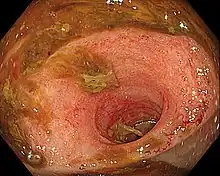

Ileitis caused by capecitabine